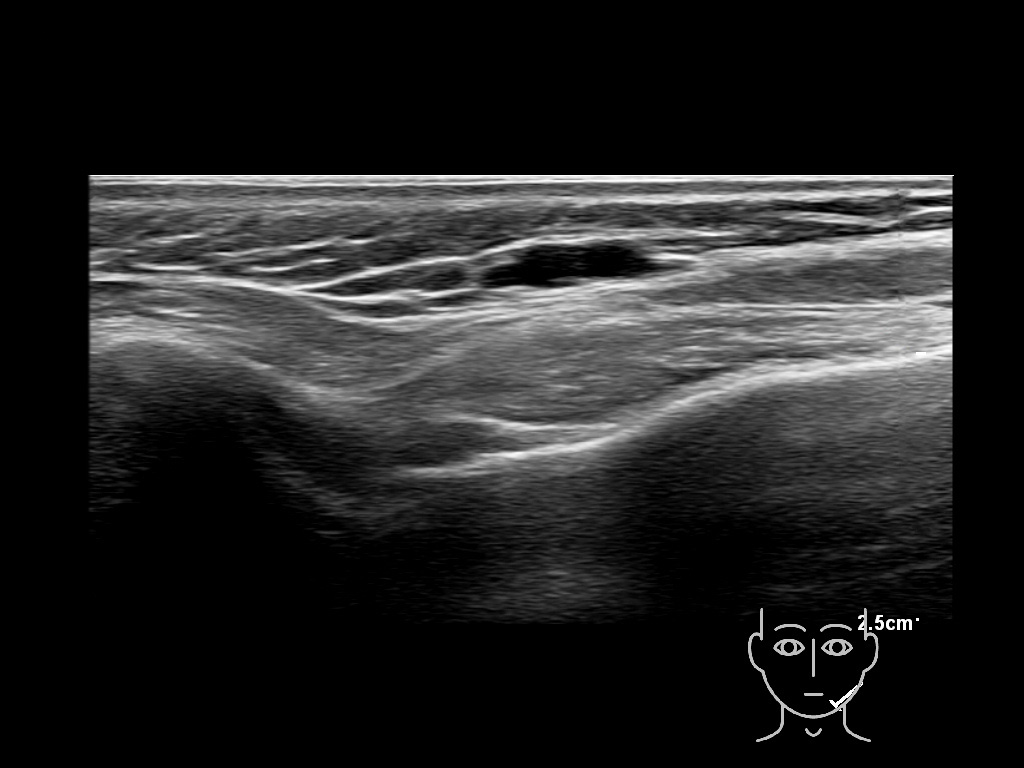

Study the first image to recognize the different layers. If you are sure about the layers, swipe to the second image to view the answer (if applicable).